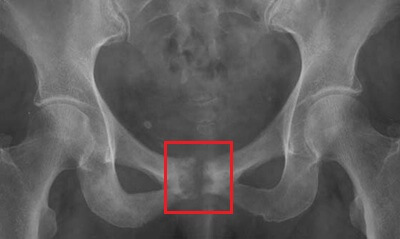

It develops where the left and right pubic bones meet at the pubic symphysis joint.

Osteitis pubis is an overuse injury that causes inflammation of the pubic symphysis, the cartilage joint that connects the two halves of the pelvis at the front.

Osteitis pubis can range from a mild irritation to a chronic inflammatory problem that limits both athletic performance and daily movement. In advanced cases, it may even cause degeneration of the joint or result in bony changes visible on imaging.

Imaging studies may be used to confirm the diagnosis or rule out other possible conditions: